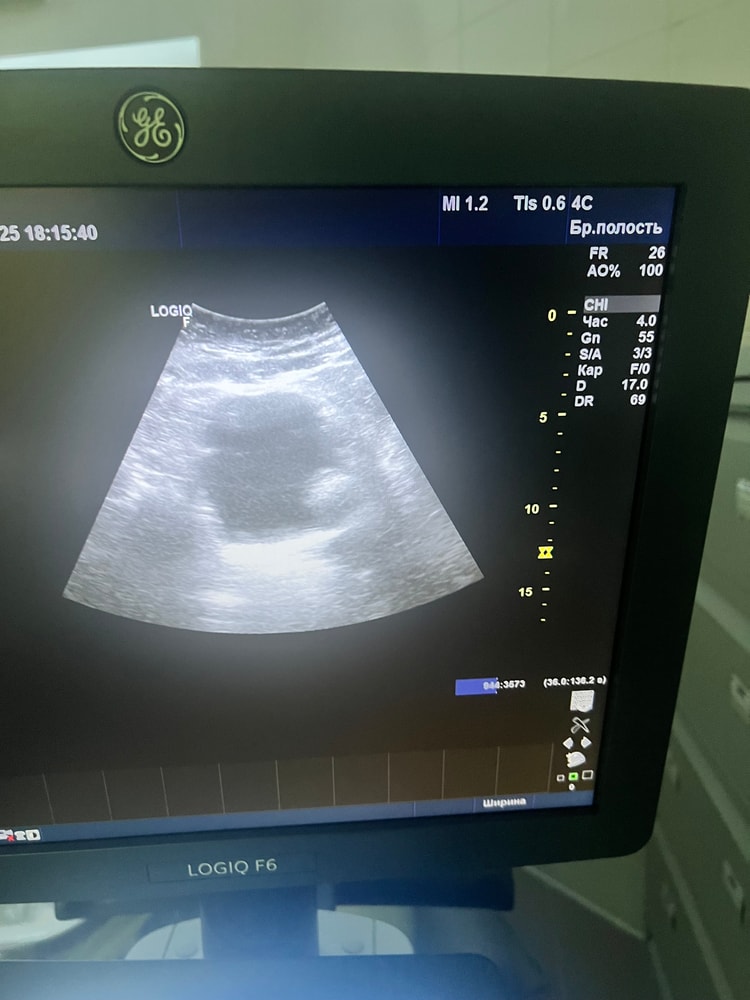

Выслеживаю овуляцию по УЗИ, девочки, подскажите ничего нет же?